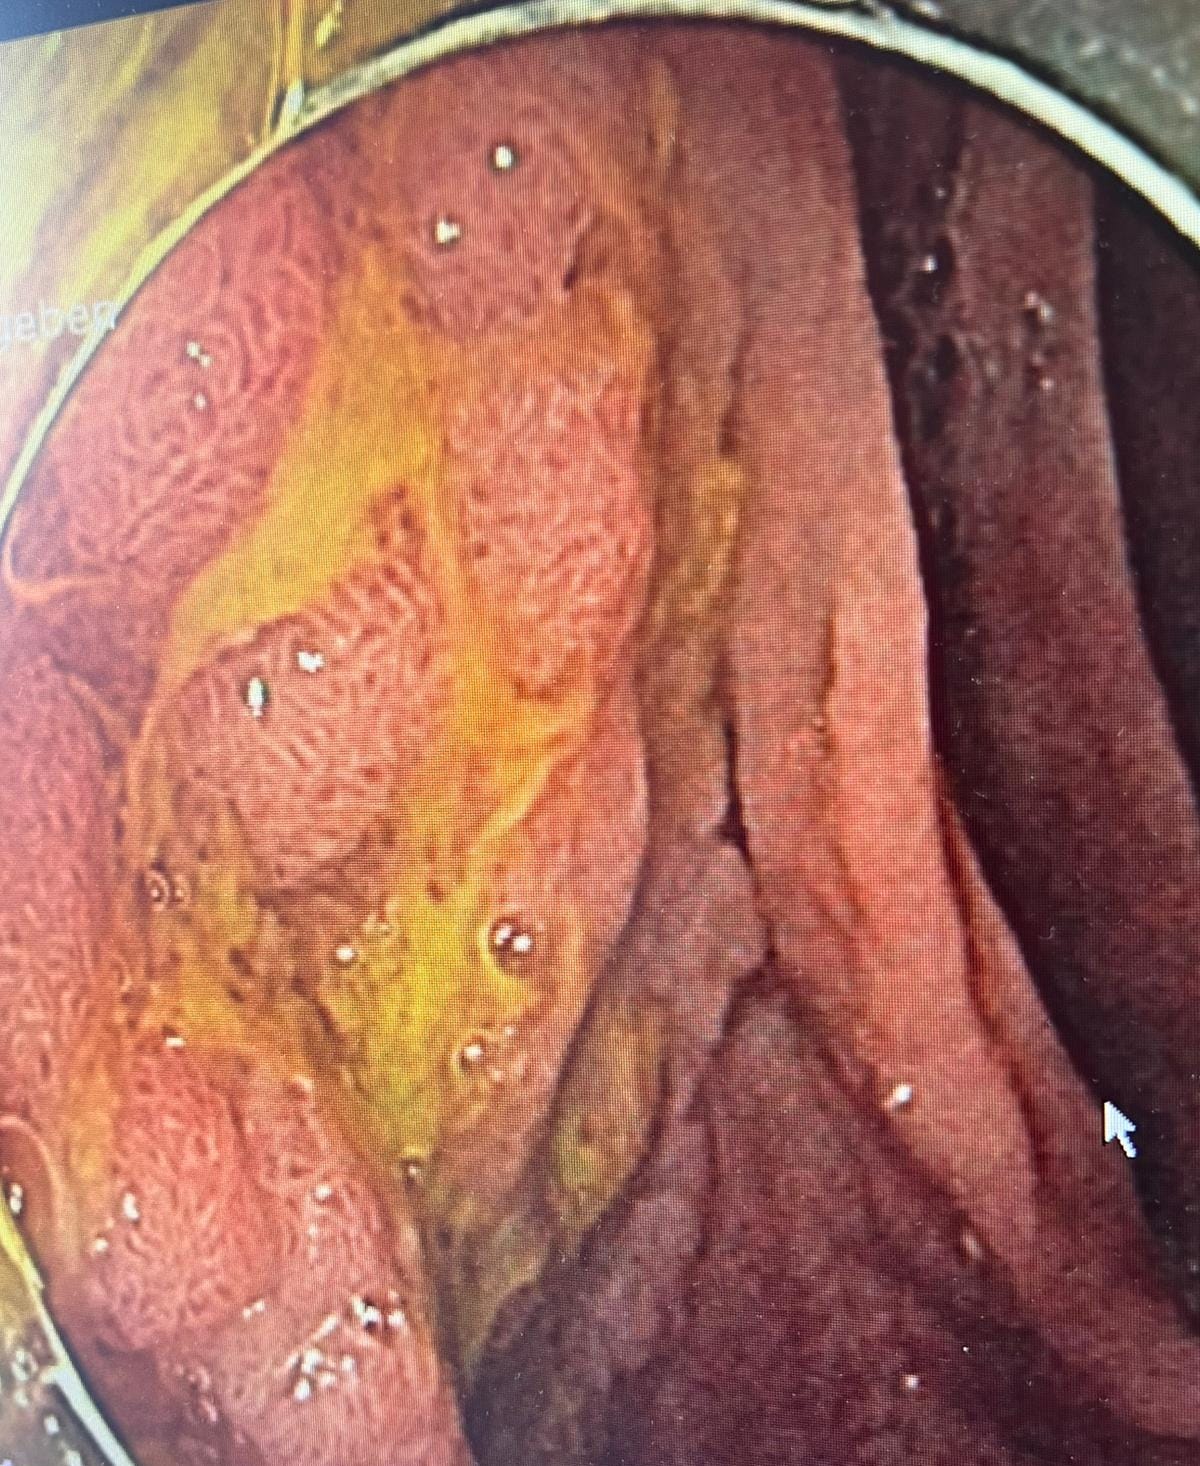

Case 5: A Puzzling Duodenum - Ischemia vs. Inflammation

Case Summary: Images of a duodenum with white-topped folds sparked a differential diagnosis discussion.

Key Teaching Points:

•Ischemia as a Possibility: The white tops of the folds raised suspicion for ischemia, a less common but important consideration.

•Inflammatory Differentials: Other possibilities discussed included chronic duodenitis with atrophic tissue or lymphangiectasia.

•Biopsy is Key: The discussion underscored that biopsy is essential to differentiate between these possibilities and make a definitive diagnosis.